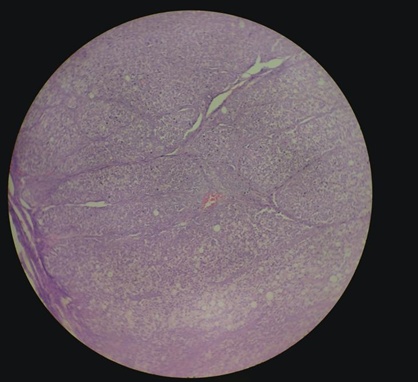

Of the 60 women who underwent a surgical procedure, histopathology of 54 specimens showed ovarian pathology. Three cases turned out to be non-ovarian pathology (paraovarian cyst) and three had normal ovarian morphology. Of the 54 cases with ovarian pathology, four had bilateral tumours so that the total number of ovarian tumours subjected to histopathological examination was 58 in all. Out of the 58 tumours, 93.10% were benign, 1.72% was borderline and 5.17% were malignant. All the malignant tumours were diagnosed as serous cystadenocarcinoma and constituted 5.17 % (fig. 1) of all the tumour cases in this study. The incidence of borderline serous tumours was 1.72% fig. 2. Surface epithelial tumors were the most prevalent among the benign tumors, accounting for 74.13% of the total. The incidence of serous cystadenomas was 44.8%, mucinous cystadenomas 22.41% (fig. 3), serous cystadeno fibromas 5.17% and mucinous cystadenoma with a component of benign Brenner’s tumor 1.72% (fig. 4). Germ cell tumours constituted 13.8% of the total, of which mature cystic teratomas accounted for 12.06% (table 4).

Fig. 1: High-grade serous carcinoma